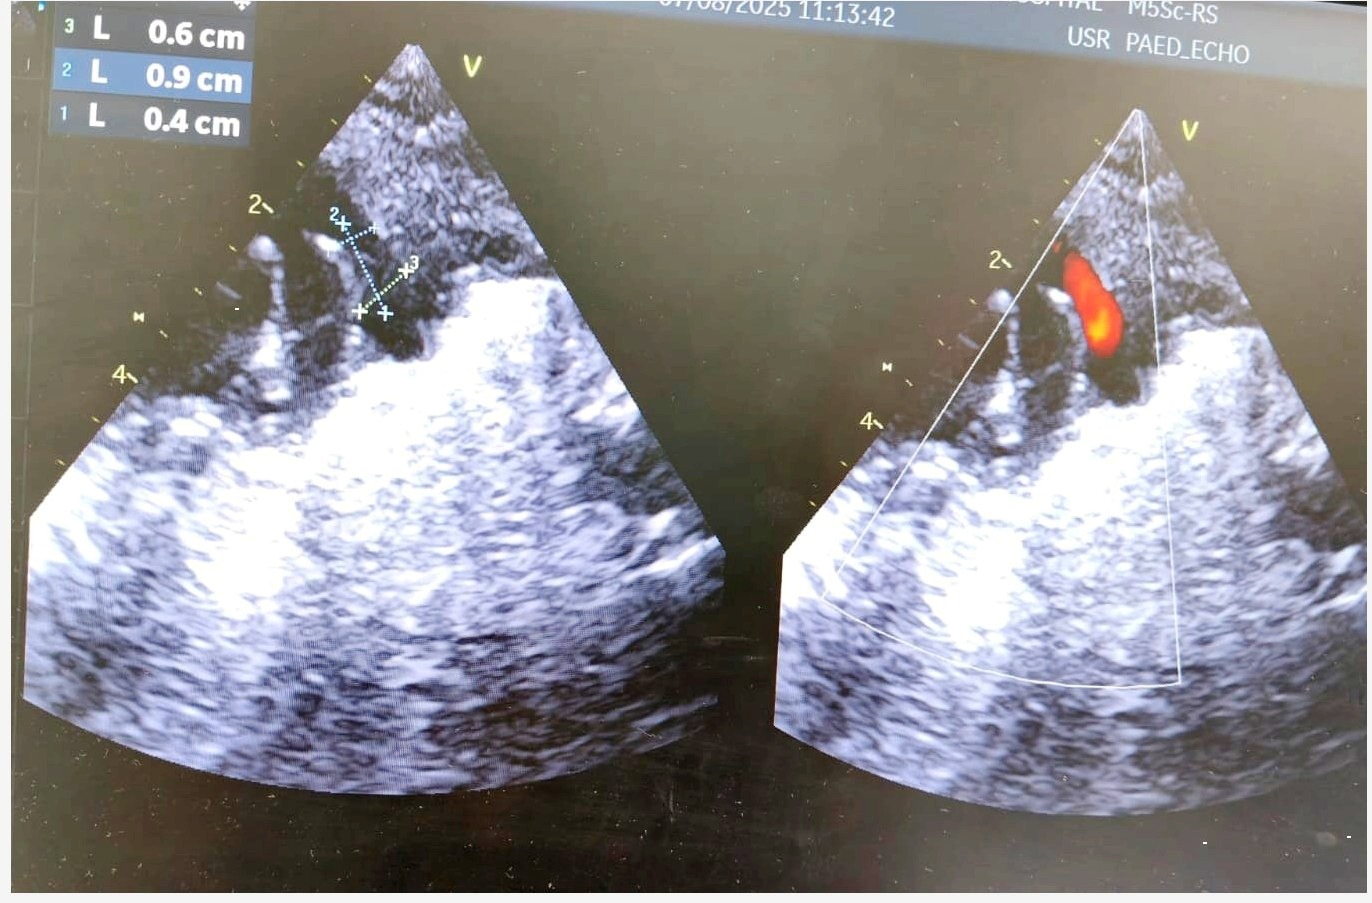

Diagnosis

Upon admission, a chest X-ray revealed cardiomegaly and pulmonary plethora, consistent with fluid overload from left-to-right shunting. An echocardiogram confirmed the presence of a hemodynamically significant PDA, classified as Type F. The ductus arteriosus had a wide opening with specific measurements: an aortic end of 6 mm, a pulmonary artery (PA) end of 4 mm, and a length of 9 mm.